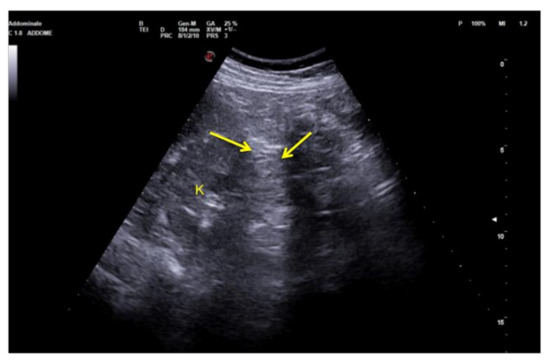

3.1.4. Refraction Artifacts

When the US beam encounters an interface that attenuates the sound to a greater or lesser extent than in the surrounding tissue, the strength of the beam distal to this structure will be either weaker or stronger than in the surrounding field [3]. This occurs because a focus material might cause the beam to deviate from its rectilinear path at an angle that causes a deflection towards the side with the higher resistance (Figure 8). Because this type of artifact can mimic a traumatic kidney rupture, it is recommended that scans are performed with coronal, axial, and sagittal pictures in order to overcome this interpretation deficiency (Figure 9) [5,6].

Figure 9. Coronal images of the left flank. Refraction of the US beam at the lower pole of the spleen causes apparent disruption of the of the middle third of the left kidney (arrows). K: kidney.